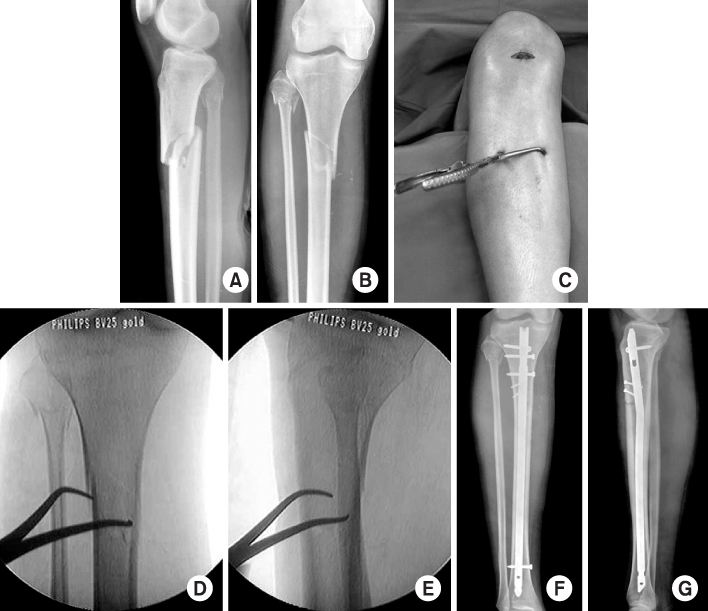

Fig. 9

(A, B) Initial radiographs show the segmental fracture of the proximal and distal tibial shafts.

(C, D) The proximal fracture was reduced and stabilized with a 1/3 tubular plate through a small incision before locked tibial nailing to prevent malalignment. Postoperative radiographs show anatomical alignment of the fracture fixed with a locked nail and a small plate.

(E, F) Radiographs 7 months after surgery show the healed fracture with external callus in good alignment.

Fig. 9 (A, B) Initial radiographs show the segmental fracture of the proximal and distal tibial shafts. (C, D) The proximal fracture was reduced and stabilized with a 1/3 tubular plate through a small incision before locked tibial nailing to prevent malalignment. Postoperative radiographs show anatomical alignment of the fracture fixed with a locked nail and a small plate. (E, F) Radiographs 7 months after surgery show the healed fracture with external callus in good alignment.